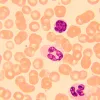

Prekė gali skirtis nuo pavaizduotos paveikslėlyje. Nuotraukoje gali būti dalių, kurios neįtrauktos į gaminio komplektaciją.

MAGUS Bio 250B biologinis mikroskopas yra optinis instrumentas, skirtas ploniems skaidriems ir peršviečiamiems objektams tirti. Ryškaus lauko mikroskopija perduodamoje šviesoje yra pagrindinis mikroskopijos metodas. Mikroskopas gali būti aprūpintas papildomais priedais tamsaus lauko, fazinio kontrasto ir poliarizacijos technikoms naudoti. Aukštos kokybės optika su papildomomis galimybėmis išplėsti savo galimybes, paprasta naudoti mechanika ir protingas dizainas daro šį mikroskopą puikiu pasirinkimu laboratoriniams darbams, tyrimams ir mokymui.